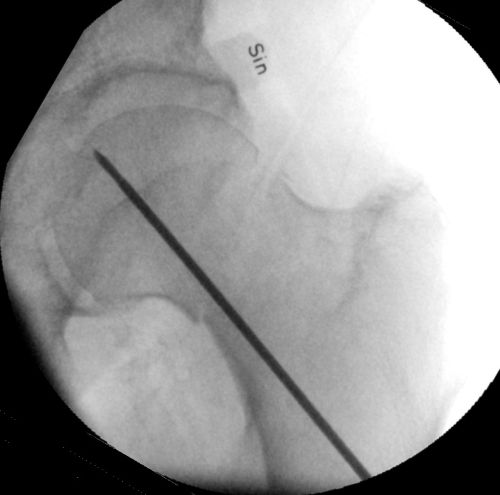

- Låt borret sitta kvar, använd distanshylsan, vinkla hylsan så det andra hålet i sidobild kommer nära dorsala kortex. Se till att komma nära kalkar, ha hög hastighet på borret och för in borret långsamt, annars är det risk att borret viker av när det ligger mot kalkar.

Genomlysning, läge för andra borrning. En k-tråd hålls över andra borret för att kontrollera placeringen.

- Läs av längden på borren. Det ser olika ut vid olika hylsor, antingen mot hylsans kant eller i hålet i hylsan. Avrunda även här uppåt och välj denna längd på spik. Den proximala/dorsala spiken brukar vara ca 10 mm kortare än den distala.